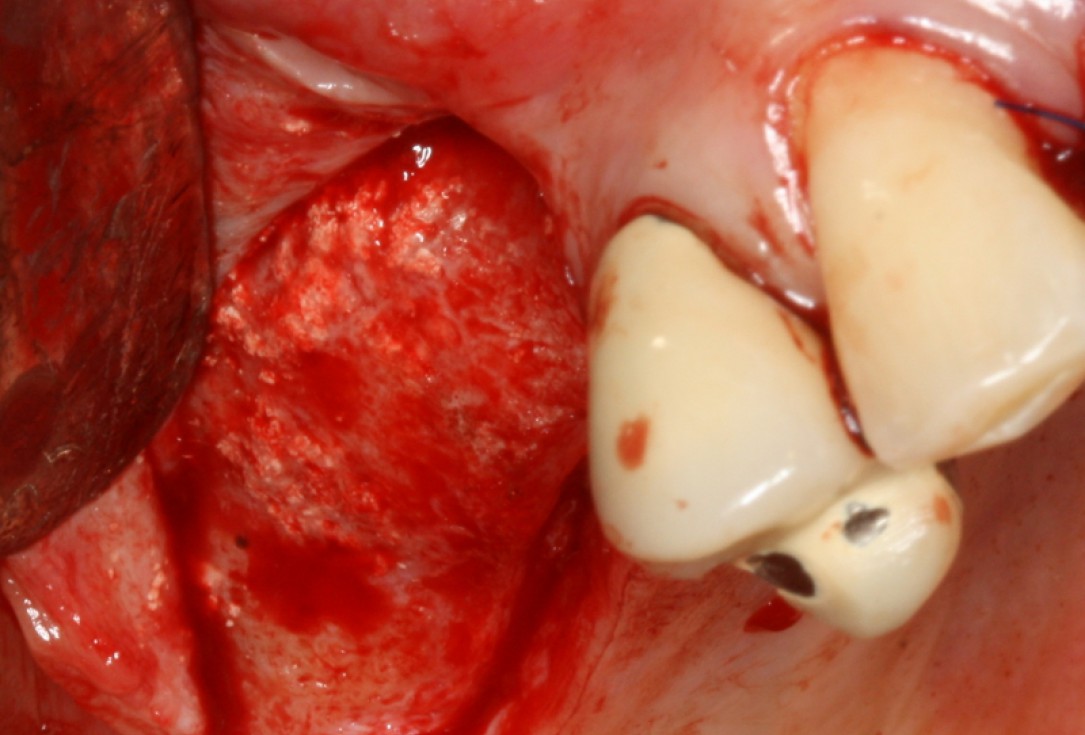

08/20 - Surgical presentation of the alveolar ridgeGBR with maxresorb® & Jason® membrane - Prof. Dr. Dr. D. Rothamel

Surgical presentation of the alveolar ridge with reduced amount of horizontal bone available